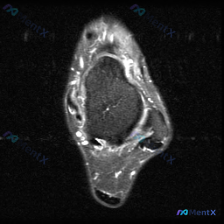

本次分析基于一张踝关节MRI轴位T2序列图像,提出的核心观察是「软组织液体」,我们结合影像特征一步步拆解:

- 骨性结构:距骨体、内踝、外踝形态完整,骨髓信号没有异常高信号,排除明显骨折、骨髓水肿或肿瘤浸润

- 关节间隙:清晰无增宽,没有明显关节腔积液

- 肌腱韧带:腓骨长短肌腱、内踝周围肌腱群、跟腱、前侧肌腱走行连续,信号均匀,外踝腓骨长短肌腱周围没有高信号积液,跟腱形态完整,当前层面内外侧韧带没有明显撕裂或水肿信号

- 软组织与神经血管:皮下脂肪和肌肉没有弥漫性水肿,没有异常占位,也没有看到血管神经的明显异常

初步影像结论:这张图像上未见显著的踝关节病理改变